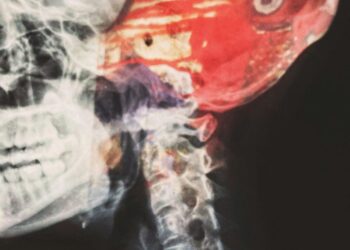

CSF Cerebrospinal Fluid: The Liquid Cushioning Your Brain